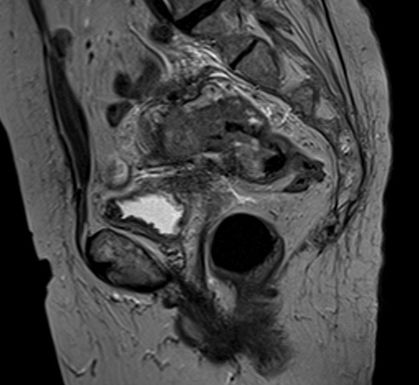

Удаление всех органов малого таза

Эвисцерация (экзентерация) малого таза >>>